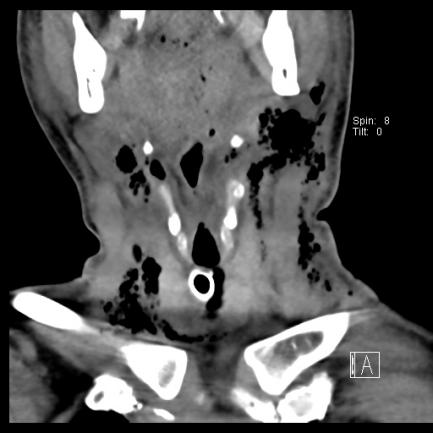

▲治疗前颈部(冠状位),胸部(轴位)

耳鼻喉科蒋锐主任会诊后考虑口腔颌面、颈部、纵隔多发感染导致的喉梗阻及感染性休克,局部穿刺得脓后更明确了诊断。